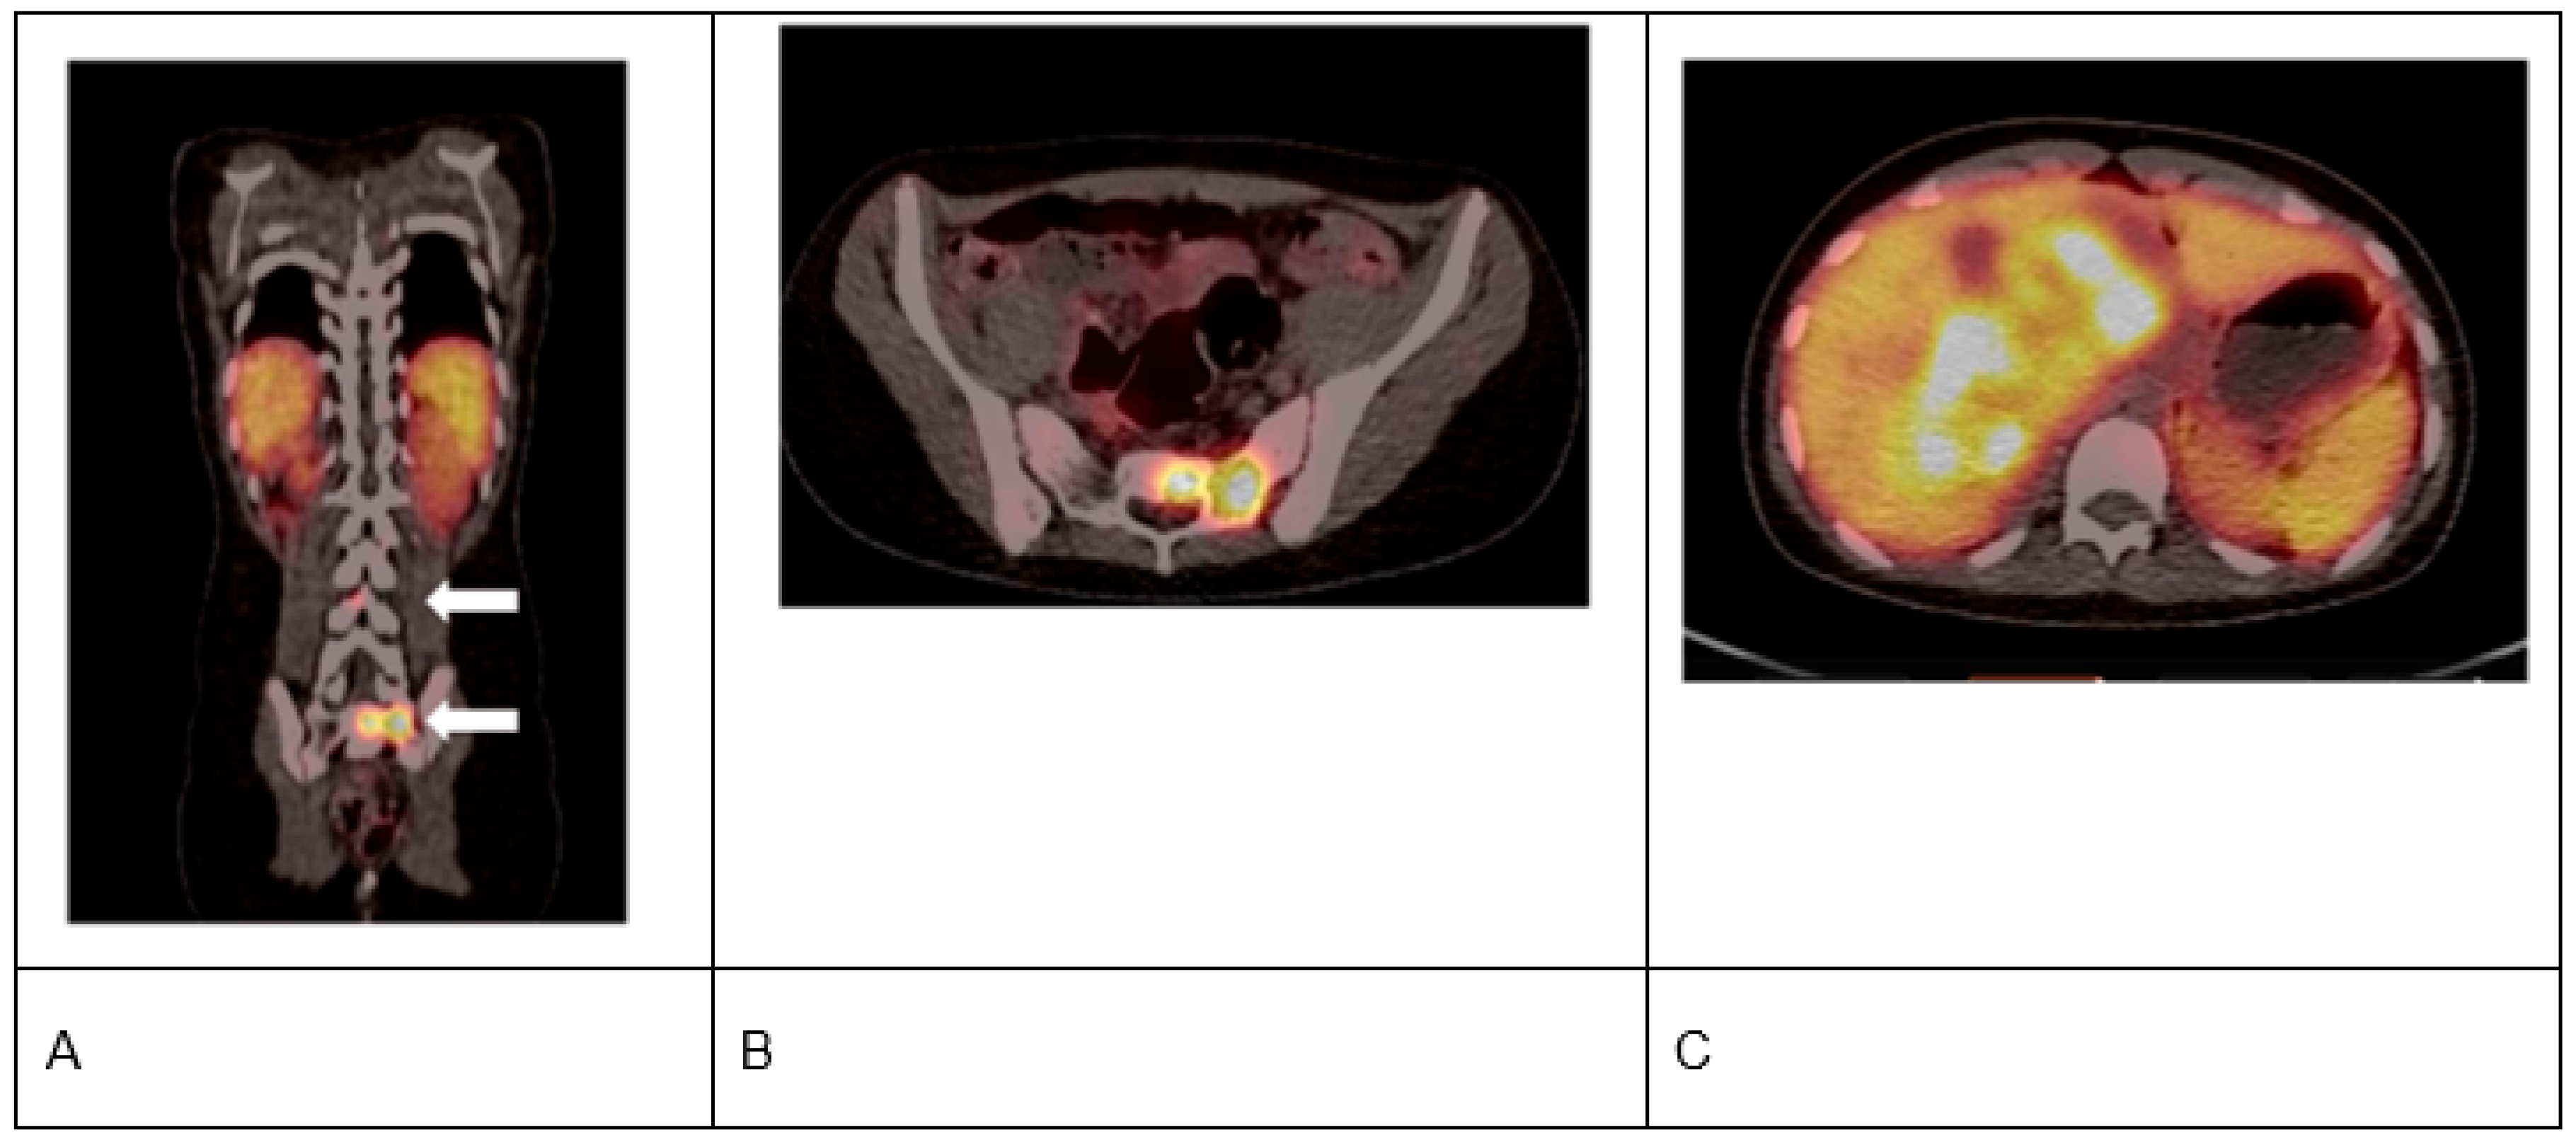

- Kong, G.; Hofman, M.S.; Murray, W.K.; Wilson, S.; Wood, P.; Downie, P.; Super, L.; Hogg, A.; Eu, P.; Hicks, R.J. Initial experience with gallium-68 DOTA-octreotate PET/CT and peptide receptor radionuclide therapy for pediatric patients with refractory metastatic neuroblastoma. J. Pediatr. Hematol. Oncol. 2016, 38, 87–96. [Google Scholar] [CrossRef]